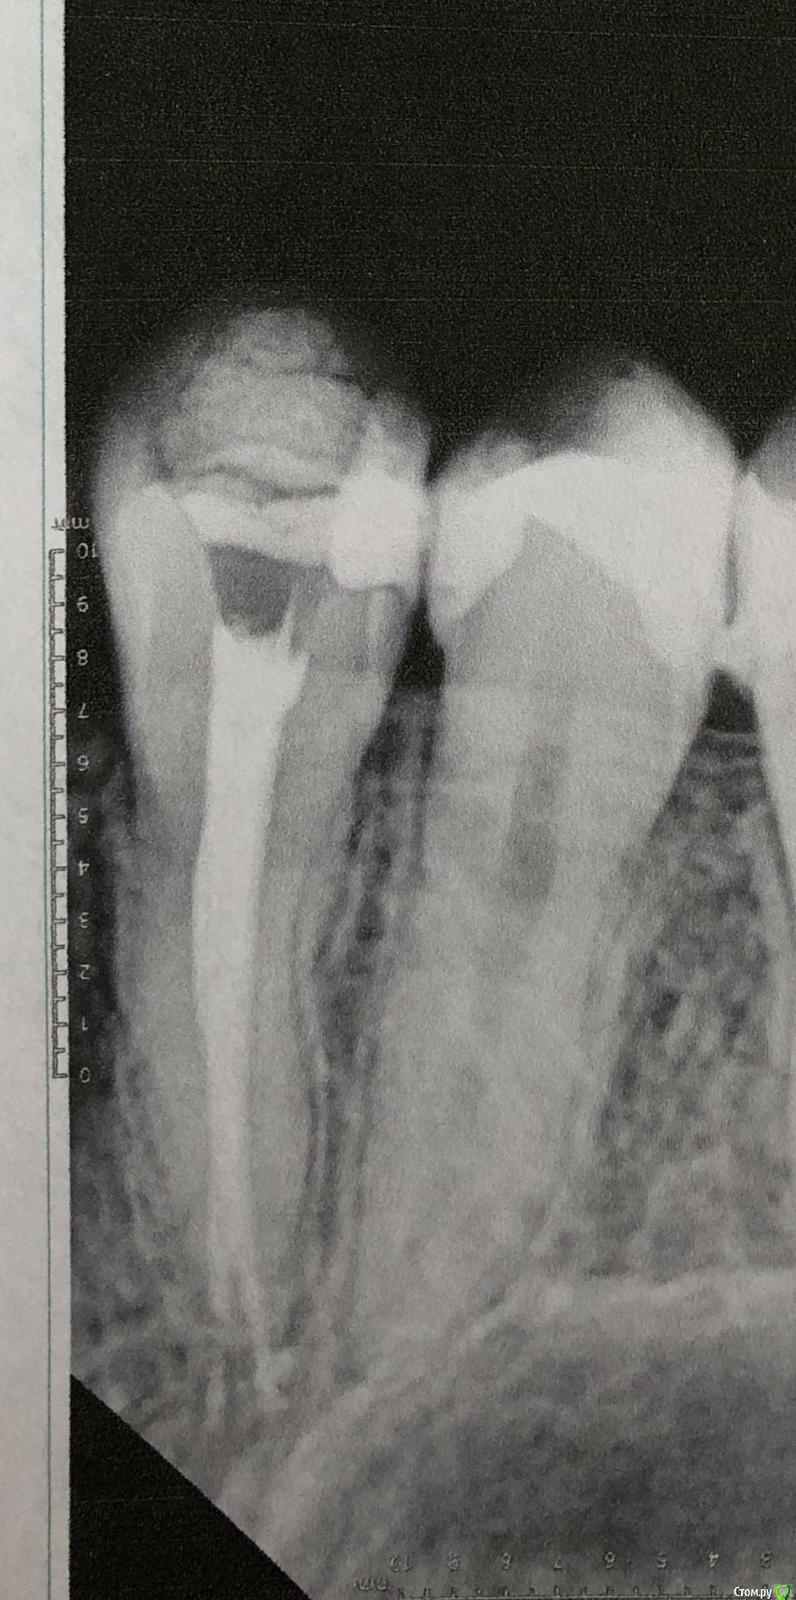

Olga2396 Опубликовано 4 ноября, 2019 Автор Поделиться Опубликовано 4 ноября, 2019 Пишу почти через месяц. пломбу переделали, но блин 5й зуб реагируете на холодное все так же, при длительной нагрузке ноет. Где десна воспаляется периодически,зубная нить рвётся.Сказал врач что может отдавать так 4й, мол там корни рядом друг с другом.Сделали снимок, сказали все нормально. Но! Я боюсь меня обманывают, потому что что-то идёт не так. Если сравнить предыдущие снимки. То на 4ке у корня какое то затемнение в месте выведение материала,на предыдущих снимках такого не было. Но 4й зуб вроде не беспокоит. 5й после холода но не длительный дискомфорт, только при перкуссии и то не всегда как то, как будто если на определенный участок зуба попадёт,твёрдая пища.Что можете сказать по этому снимку? На счёт 4го и 5го.Если сравнить предыдущие. Ссылка на комментарий

Olga2396 Опубликовано 4 ноября, 2019 Автор Поделиться Опубликовано 4 ноября, 2019 (изменено) Прошу незакидывать камнями,а дочитать историю до конца и войти у мое положение.Мне зуб с гранулемой,ссылку прилагаю лечат уже почти 5 месяцев, мне кажется меня обманывают и губят мое здоровье. Кт сделано 5 месяцев назад. Сначала она врач распломбировала каналы,промывала,использовала изначально рабедарм(изоляцию),заводила лекарство. После первых манипуляций первые 5 дней, а началась я лечиться в июне, я лезла на стенку от боли,но потом боли прошли, второй раз она промыла каналы через 2 недели закладывала лекарства метапекс какой-то и каласепт,за эти 2 раза зуб вроде стих,но у меня начались проблемы с другими зубами. На снимке видно что был пульпит нижнего 6го зуба,этот зуб вроде залечили. С гранулемой забыли. чрез 2 недели его надо бы уже закрыть, но мне его раскрыли промыли(последующие разы уже не применялся рабедарм)и вроде заложили лекарство, но как оказалось нет. Тут врач неожиданно уезжает на месяц. Через недели 2 у меня зуб с гранулемой начинает снова болеть, при надкусывании, реакция на горячее, я пишу ей, она говорит дождись меня. За это время она прописала мне антибиотики амоксиклав, я пропила,стала легче. Но ненамного.Она приезжает и у меня начинаются проблемы со следующими зубами, как раз 4 и 5, там был глубокий кариес. В 4м удалили нерв, хотя он не болел, нотреагировал на холодное и сладкое,не было таких пульпитах болей, 5й долго не залечивали, так как появилась новая проблема. 6й зуб который был снизу с пульпитом, боли не проходили (первая ссылка до перелечивания) ,при постукивании болел, при нажатии болел, иногда самопроизвольно болел. Переличили, сменила пасту пломбировочную и сказала что до этого была паста ah+ И сказала запломбировала эндометазоном (после лечения) . я снова жалуюсь на зуб с гранулемой тут опять она снова берётся за 6 промывает,зуб месяц был пустым оказывается и закладывает почему то в один канал гуттаперчевый штифт с каким то лекарством и снова уезжает куда то на две недели. за эти 2 недели боли стихли но началась проблема с 4м зубом который изначально лечили также Ah + он начал дико реагировать на горячее, до зуба было не дотронуться. я ей звоню опять же она говорит ждать ее, я свято верила ей,пока мое лечение не затянулось до настоящего момента,поэтому всю историю излагаю здесь. Она приезжает перелечивает зуб 4й и боли моментально проходят, в этот же день, на что она мне говорит что запломбировала очень хорошим французским лекарством под названием эндометазон с гуттаперчевыми штифтами,что мол,он якобы с противомикробный действием и даже если там что то осталось,эндометазоном убьёт микроорганизмы. Не знаю так ли это. Проблемы с зубом с гранулемой остались все так же нерешенными по сей день, а прошло 5 месяцев. Когда я уже пришла и сказала давайте как то уже будем решать вопрос с зубами и будем иметь хоть какую то монотонную работу, она прям реально так с особой серьезностью сказала что дада щас заложим лекарство и запломбируем его скоро. Назначили встречу она промывает мне зуб за 15 минут и отпускает говорит все. Теперь через 3 недели,мол типа в отпуск ухожу на следующей неделе. Я тогда подумала ну ладно, кальций она вроде мне заложила. Как оказалось всего в 2 канала, я это увидела по снимку и спросила почему так. Она сказала в другие смысла нет закладывать и она делала так ПОСТОЯННО. Там нет воспаления. Но через 4 дня почему зуб начал реагировать снова на горячее,боль была как будто по самим границам колонковой части, а не на середине жевательной поверхности зуба.Надкусить было неприятно не сказать что больно, о своих ощущениях она говорила сообщать,ну я и сказал, а так как она собралась идти в отпуск она передаёт меня другому врачу. Все это реально затянулось на 5 месяцев. (Я могла прийти на приём к ней, а она уйти или так же снова уехать куда то на неделю на две и лечение ещё затягивалось на неделю. Я рассказала малую часть, встречи переносили и лечение затягивалось,затягивалось, пока не привело меня сюда и сомнения в её квалификации или желании вылечить мои зубы.) Следующий врач говорит что все это затянулось и говорит слишком долго зуб был открыт без пломбировки. Промывает мне его, пробивает каналы и говорит что у меня там гной типа, тянется за сухими штифтами, и что странное я не знаю кому верить, та врач которая щас в отпуске говорит что там налёт на каналах типа творога, а эта врач говорит что там не налёт а «сопли» каки то тянется из двух каналов. И что ещё более странное у врача которая в отпуске длинна каналов была 17,18. А у этой 15,14 Как может расходиться длинна каналов? Он же у меня не изменяется за весь период...кому верить? Измеряли обе аппекслокатором... последний снимок зуба с гранулемой когда последний раз промыли мне зуб, 2 дня было хорошо все. А на 3й начались такие боли, что не то что надкусить, он у меня пульсировал так что не помогали обычные таблетки типа ибупрофена, помог только кеторол.+ ещё вопрос. У меня зуб который 6 снизу был с пульпитом периодически будто бы простреливает в районе между 5,6. Говорят что такого быть не может каналы запломбированы хорошо,но что я заметила,очень спилили коронку зуба и прикус снизился. Что скажете по снимку? Снимок в настоящее время.Простите за много слов, я очень устала от болей. Просто описала всю ситуацию. Вывод и вопросы: 1.Что делать с зубом у которого гранулема? 5 месяцев лечат,то забывают про него, то снова закладывают лекарство. В данный момент мне уже врач (к которому меня передала та которая ушла втотпуск) говорит просто в следующее посещение промоем и поставим постоянную пломбу. Я напротив но боли сейчас стали ещё сильнее, как при первом визите в июне. За все время я то забыла про зуб с гранулемой то снова вспоминала,вполне болей. Посещала я врача по расписанию. И каждый раз там снова появлялся налёт как мне говорила предыдущая врач. Нормально ли лечить зуб так долго 5 месяцев? Или это повод пойти к другому? Или пойти жаловаться вообще? Какой протокол лечения таких зубов. 2. Что с 6м снизу? Может там тоже Каналы плохо пролечены? Что периодически простреливает между 5,6 как будто. Или это десна? Или это вообще из за того что прикус снизился на этой стороне? Зуб явно если посмотреть срез Кт и снимок в настоящее время ниже чем должен был быть,может нагрузка идёт не на жевательный зуб поэтому так стреляет?3. Что с 4м депульпированный зубом сверху? там нет никаких воспалений на верхушке корня? И по 5 рядом что скажите какие прогнозы на данный момент? разница снимков в месяц Изменено 4 ноября, 2019 пользователем Olga2396 Ссылка на комментарий